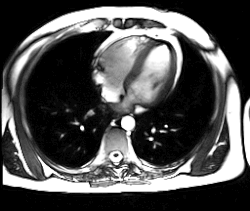

MRT-Aufnahme des schlagenden Herzens

Schlagendes Herz

Neue, schnellere Aufnahmeverfahren ermöglichen das Scannen einzelner Schnittbilder in Bruchteilen einer Sekunde und liefern auf diese Weise eine wirkliche Echtzeit-MRT, die die bisherigen Versuche in Anlehnung an die konventionelle Fluoroskopie ersetzen. Somit können beispielsweise Bewegungen von Organen dargestellt oder die Position medizinischer Instrumente während eines Eingriffs überwacht werden (interventionelle Radiologie). Zur Abbildung des schlagenden Herzens (Abbildung rechts) werden bisher mit einem EKG synchronisierte Messungen benutzt, wobei Daten aus mehreren Herzzyklen zu vollständigen Bildern kombiniert werden. Neuere Ansätze für die Echtzeit-MRT versprechen dagegen eine direkte Herzbildgebung ohne EKG-Synchronisation sowie bei freier Atmung mit einer zeitlichen Auflösung von bis zu 20 Millisekunden.

• Schnell bewegte Organe wie das Herz lassen sich mit den meisten üblichen Geräten nur mit eingeschränkter Qualität darstellen oder erfordern eine Bewegungskompensation durch zeitliche Mehrfachabtastung. Mit Multikanalsystemen und HF-Empfangsspulen mit zahlreichen parallelbetriebenen Spulenelementen sind diese Untersuchungen durch Verfahren wie die parallele Bildgebung jedoch möglich und halten mehr und mehr Einzug in die klinische Routinediagnostik.